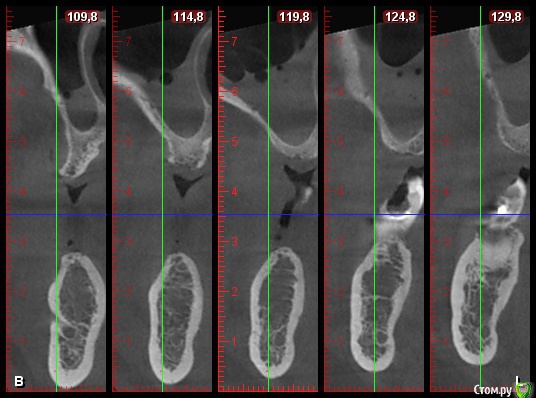

DenisV Опубликовано 11 декабря, 2017 Поделиться Опубликовано 11 декабря, 2017 Доктора, пациент обратился с целью установки имплантатов. На клКТ обнаружено затенение пазухи, отправлен к ЛОР на консультацию. Что это? синусит? ретенционка? Ссылка на комментарий

Большой Зеленый Опубликовано 12 декабря, 2017 Поделиться Опубликовано 12 декабря, 2017 Гайморит . 5 Ссылка на комментарий

Paganini Опубликовано 12 декабря, 2017 Поделиться Опубликовано 12 декабря, 2017 (изменено) Это синусит. И жалоб нет? Изменено 12 декабря, 2017 пользователем Paganini Ссылка на комментарий

колесников Опубликовано 12 декабря, 2017 Поделиться Опубликовано 12 декабря, 2017 Пузырьки газа в жидкости. Ссылка на комментарий